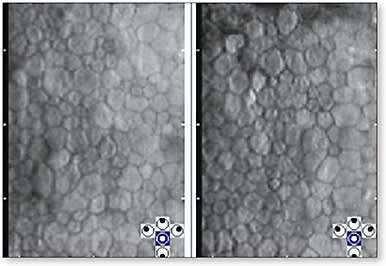

Confocal Microscopy This imaging technology has developed as a highly useful technique for the detailed study of corneal cellular structure. The basic principle of a confocal microscope involves a single point source of illumination on a single point of tissue that is simultaneously imaged by a camera in the same plane, hence the term “confocal.” Confocal microscopy is a powerful diagnostic technique that allows non-invasive microscopic examination of the cornea. However, until recently, use in clinical practice has been limited to research centers. New developments in technology have made confocal microscopy available to clinical practitioners.

The applications of confocal microscopy in ophthalmic practice are numerous and expanding as the value of these high-resolution images is realized. For example, confocal microscopy can be used to identify the causative organism in patients who have infective keratitis such as Acanthamoeba keratitis and other causes of contact lens-related keratitis. Confocal microscopy also seems to have relevance in the deeper understanding of keratoconus, glaucoma, and dry eye/ocular surface disease. It is highly applicable to the detection of corneal anomalies induced by contact lens wear. Confocal microscopy continues to develop, and researchers are discovering more about a variety of diseases and conditions through the use of this technology.